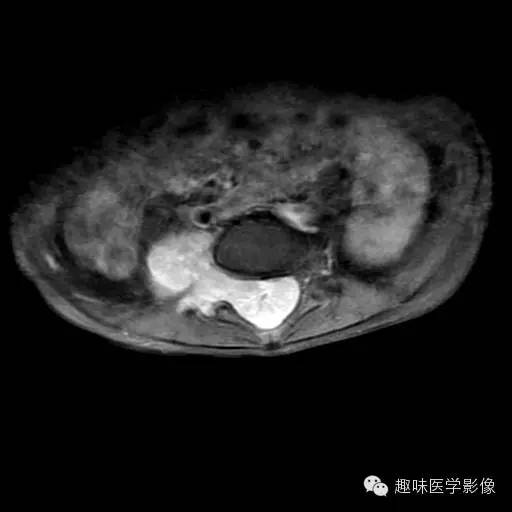

女,7岁,主因行走困难5个月。

腰4-骶3椎管内硬膜外见等T1稍长T2弥漫性生长肿块,蛛网膜下腔受压变窄,前移,硬脊膜前移,自邻近椎间孔向外生长至右侧腰大肌内后方,局部椎间孔扩大,腰大肌受压前移。

增强扫描病灶呈明显均匀强化。椎体未见骨质破坏。

恶性神经鞘瘤

本病影像学表现为孤立或弥漫生长的肿块,大小不一,部分边界清楚、可有包膜,肿瘤的信号或密度不均匀,增强扫描可见不同程度的斑块状、网格状及岛屿状强化,CT低密度或MR长T1、长T2信号不强化。肿块中心不强化提示肿瘤为恶性。

椎管内恶性神经鞘瘤的鉴别诊断主要是椎管内良性神经鞘瘤,后者一般边缘清楚、密度或信号均匀,可向一侧椎间孔延伸呈哑铃状,注射对比剂后CT及MR均可见明显及均匀或不均匀强化。

椎管内恶性神经鞘瘤少见,病变进展较快,为弥漫浸润性生长,瘤内信号或密度不均,应列为椎管内髓外硬膜下肿瘤的鉴别诊断范围。